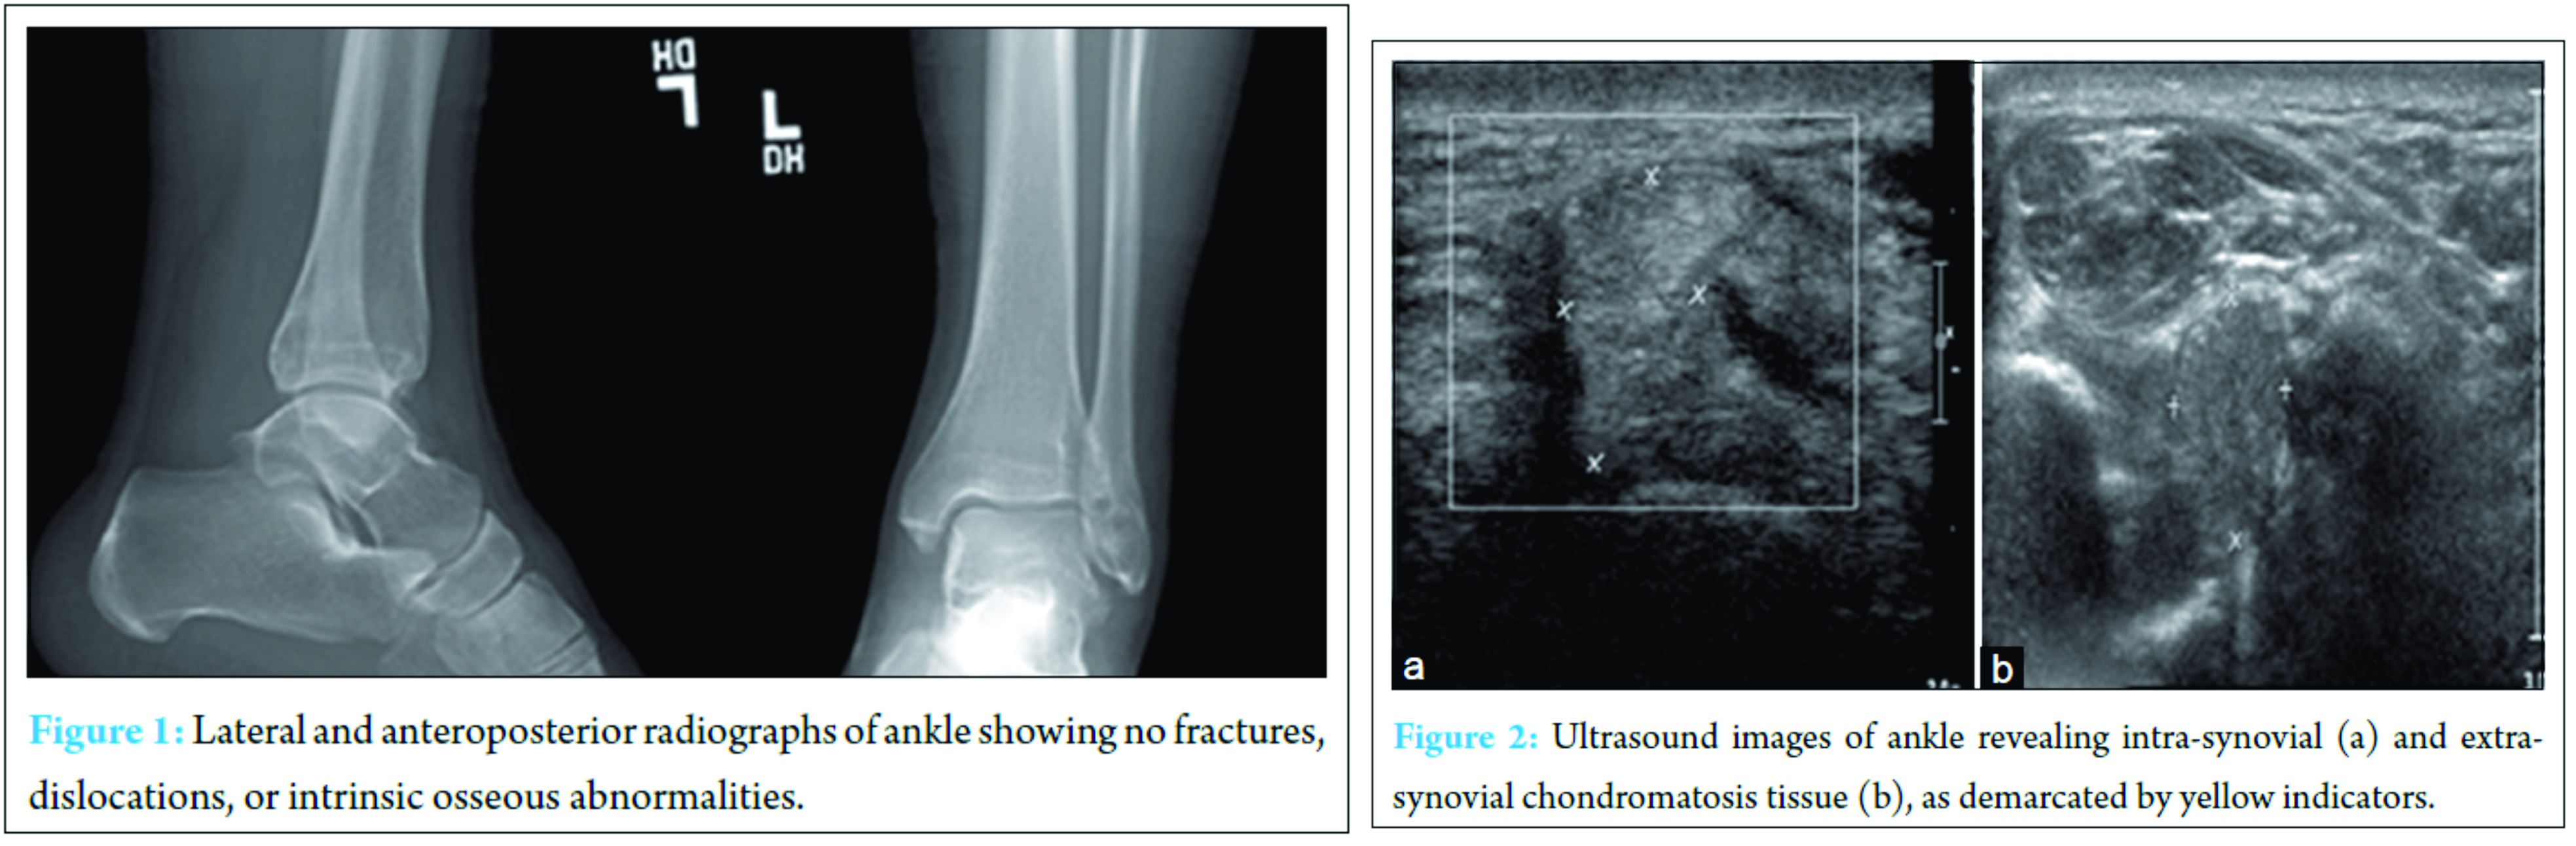

Two years after that first operative intervention, the patient returned with left ankle pain and swelling aggravated by shoe-wearing, weight bearing, and climbing stairs. He also reported symptoms consistent with tarsal tunnel syndrome in the same foot – tingling and burning along the plantar aspect of his foot. Physical examination at this time demonstrated palpable fullness of the ankle joint with minimal restriction in range of motion as well as exquisite tenderness to palpation anterolaterally. A palpable mass was noted along the anterolateral aspect of the ankle. His motor and sensory exams were within normal limits and range of motion of the ankle, and subtalar joints were within normal limits. Radiographs obtained demonstrated opacity overlying the pre-Achilles fat pad and adjacent soft tissues of the posterior ankle (Fig. 1). There was moderate erosion of the anterolateral aspect of the distal tibia. No fractures, dislocations, or intrinsic osseous abnormalities were noted. Ultrasound of the left ankle revealed distention of the joint capsule anteriorly and posteriorly at the tibiotalar joint with intra-articular debris as well as hyperemia of the synovium (Fig. 2). The anterolateral gutter also had intra-articular debris and was distended. Magnetic resonance imagining (MRI) demonstrated numerous large, lobulated, heterogeneously enhancing lesions posteriorly surrounding the flexor hallucis longus (FHL) tendon, and extending into the anterior tibiotalar joint (Fig. 3). There was minimal involvement of the sinus tarsi; however, cranial extension between the distal tibiofibular syndesmosis was noted along with stable erosion of the anterolateral aspect of the distal tibia. The tendons and ligaments of the left ankle were intact, and the articular cartilage was unremarkable. No soft tissue swelling, edema, or bony involvement was identified. These findings were consistent with the MRI findings from his primary presentation 2 years ago (Fig. 4). Extensive ankle joint T2-signal abnormality was consistent with recurrence of synovial chondromatosis. Following this rediagnosis, the patient was scheduled for ankle arthroscopy with joint decompression and synovial debridement.